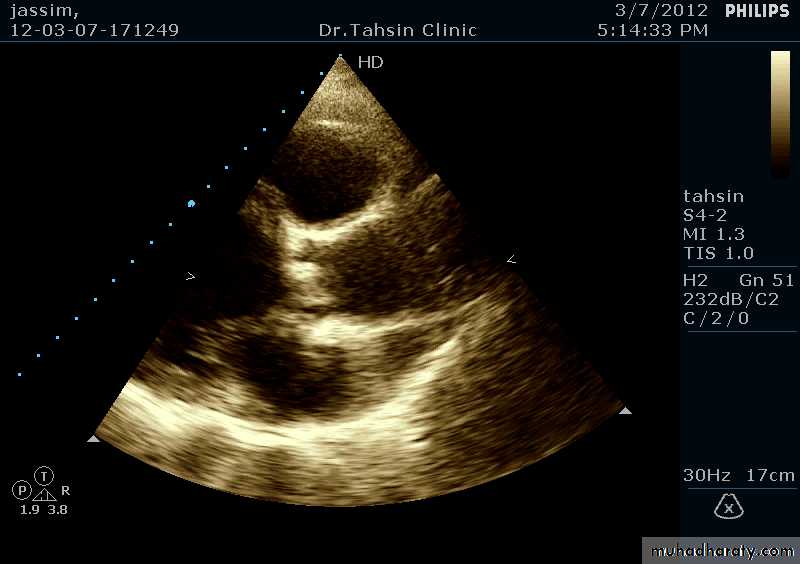

Two Dimensional Echocardiography

Ultrasound beam passing through the heart generates cross sectional images or “slices” of the heartVarious structures can be seen in real time

Two Dimensional Echocardiography indications

Assessment of LV functionDiagnosis & quantitation of severity of valvular lesions

Identification of vegetations

Identifying the source of systemic embolism

Detection of pericardial effusion

Doppler Echocardiography

Sound waves reflected from moving RBCs undergo frequency shiftThe faster the blood velocity , the greater the frequency shift

The direction of moving blood determines whether the reflected signal is positive or negative

The derived signal can be plotted graphically against timeOr, color can be assigned for the reflected signal and superimposed over the 2D image (color flow mapping)